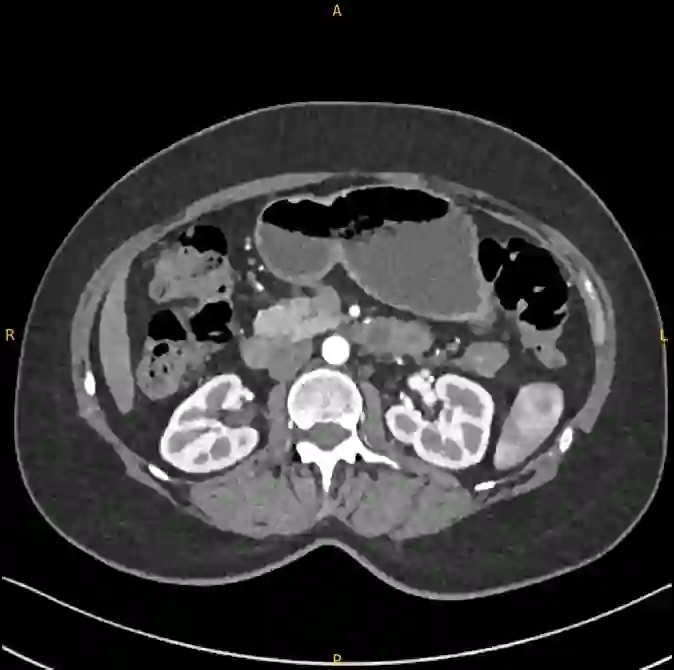

Pancreatic ductal adenocarcinoma (PDAC), one of the deadliest solid malignancies, is often detected at a late and inoperable stage. Retrospective reviews of prediagnostic CT scans, when conducted by expert radiologists aware that the patient later developed PDAC, frequently reveal lesions that were previously overlooked. To help detecting these lesions earlier, we developed an automated system named ePAI (early Pancreatic cancer detection with Artificial Intelligence). It was trained on data from 1,598 patients from a single medical center. In the internal test involving 1,009 patients, ePAI achieved an area under the receiver operating characteristic curve (AUC) of 0.939-0.999, a sensitivity of 95.3%, and a specificity of 98.7% for detecting small PDAC less than 2 cm in diameter, precisely localizing PDAC as small as 2 mm. In an external test involving 7,158 patients across 6 centers, ePAI achieved an AUC of 0.918-0.945, a sensitivity of 91.5%, and a specificity of 88.0%, precisely localizing PDAC as small as 5 mm. Importantly, ePAI detected PDACs on prediagnostic CT scans obtained 3 to 36 months before clinical diagnosis that had originally been overlooked by radiologists. It successfully detected and localized PDACs in 75 of 159 patients, with a median lead time of 347 days before clinical diagnosis. Our multi-reader study showed that ePAI significantly outperformed 30 board-certified radiologists by 50.3% (P < 0.05) in sensitivity while maintaining a comparable specificity of 95.4% in detecting PDACs early and prediagnostic. These findings suggest its potential of ePAI as an assistive tool to improve early detection of pancreatic cancer.

翻译:胰腺导管腺癌(PDAC)作为致死率最高的实体恶性肿瘤之一,常在晚期且无法手术的阶段才被检出。回顾性分析诊断前的CT扫描时,若由知晓患者后续确诊PDAC的资深放射科医师审阅,常可发现先前被忽略的病灶。为助力更早发现这些病灶,我们开发了一套名为ePAI(基于人工智能的早期胰腺癌检测)的自动化系统。该系统使用来自单一医疗中心的1,598名患者数据进行训练。在包含1,009名患者的内部测试中,ePAI在检测直径小于2厘米的小型PDAC时,受试者工作特征曲线下面积(AUC)达0.939-0.999,灵敏度为95.3%,特异度为98.7%,并能精确定位小至2毫米的PDAC。在涵盖6个中心、7,158名患者的外部测试中,ePAI的AUC为0.918-0.945,灵敏度达91.5%,特异度为88.0%,可精确定位小至5毫米的PDAC。尤为重要的是,ePAI在临床诊断前3至36个月获取、曾被放射科医师漏诊的诊断前CT扫描中成功检测出PDAC。在159名患者中,系统成功检测并定位了75例PDAC,中位领先临床诊断时间达347天。我们的多阅片者研究表明,在早期及诊断前PDAC检测中,ePAI的灵敏度显著优于30名具备执业资格的放射科医师50.3%(P < 0.05),同时保持95.4%的可比特异度。这些发现表明ePAI具备作为辅助工具提升胰腺癌早期检测能力的潜力。